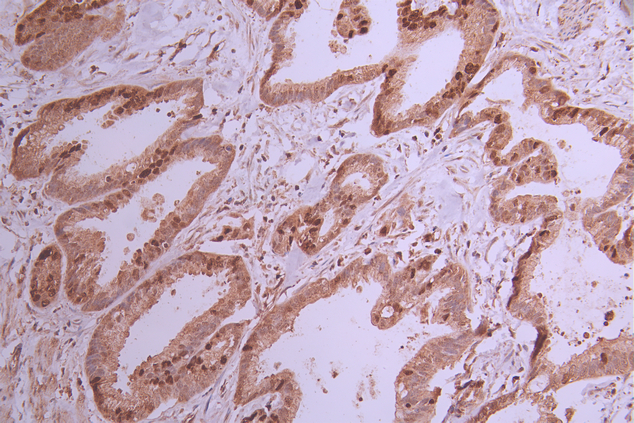

IHC image of CSB-RA986091A0HU diluted at 1:100 and staining in paraffin-embedded human cervical cancer performed on a Leica BondTM system. After dewaxing and hydration, antigen retrieval was mediated by high pressure in a citrate buffer (pH 6.0). Section was blocked with 10% normal goat serum 30min at RT. Then primary antibody (1% BSA) was incubated at 4°C overnight. The primary is detected by a Goat anti-rabbit polymer IgG labeled by HRP and visualized using 0.05% DAB.